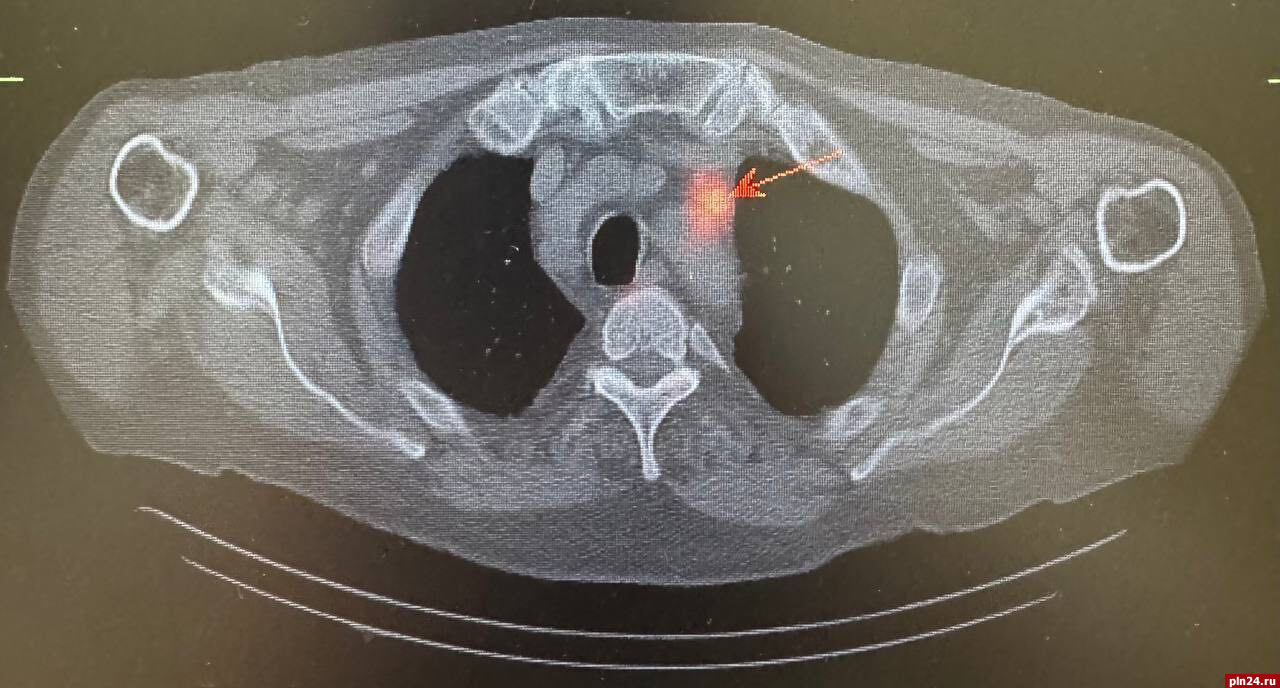

Результаты компьютерной томографии органов грудной клетки выявили наличие внутригрудных лимфатических узлов, которые выглядели подозрительными на предмет метастатического поражения. Однако, кроме этого, значимых вторичных изменений в других органах не обнаружили.

Для уточнения диагноза и получения более детальной информации о состоянии лимфатических узлов была назначена радионуклидная диагностика. Этот метод позволил более точно определить наличие злокачественного опухолевого процесса в предстательной железе, а также подтвердить метастатическое поражение ранее выявленных лимфатических узлов в грудной клетке. Кроме того, радионуклидное исследование показало активное накопление технеция ПСМА в парааортальных лимфатических узлах с обеих сторон.